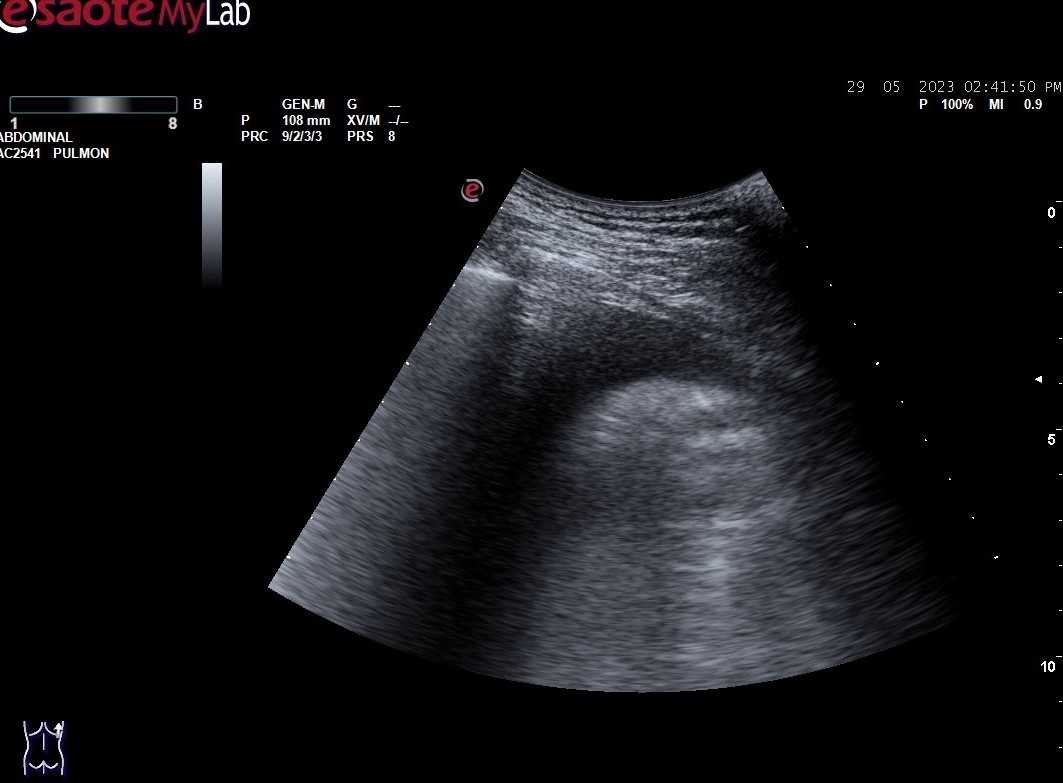

Hallazgos ecográficos

Hallazgos ecográficos: derrame pleural bilateral y abundantes líneas B (más de 3 por espacio intercostal) en ambos 1/3 medios inferiores bilaterales (adjuntamos imágenes).

En la ecografía pulmonar observamos unos patrones ecográficos (normal, deslizamiento pleural, líneas A, líneas B, derrame pleural y consolidación pulmonar). Realizando una serie de preguntas dicotómicas sobre estos patrones ecográficos se establece un algoritmo (protocolo BLUE) que permite establecer con alta sensibilidad y especificidad la causa de la disnea mediante un árbol de decisión.

Aplicando dicho protocolo establecemos un diagnóstico ecográfico de presunción de Edema Agudo de Pulmón/Insuficiencia cardíaca.